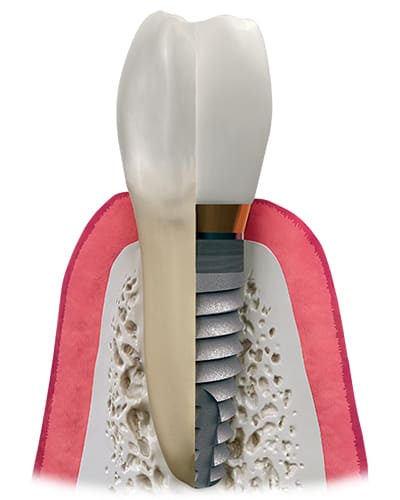

一生もののインプラント

逗子海岸歯科では、世界的な学術研究に基づき開発、世界70か国以上で使用され、大学病院でも広く採用されている、最も信頼性を重視した世界的インプラントメーカーであるストローマン(Straumann)システムを用いて治療を行っています。

インプラントは入れ歯と違い、しっかり骨と結合するため、噛む機能が回復し、通常の食生活を堪能できます。

インプラントは、ブリッジや入れ歯のように周りの歯を削ったり、きれいな歯を傷つけることはありません。また、無歯による周りの歯の骨吸収を防ぐことができます。